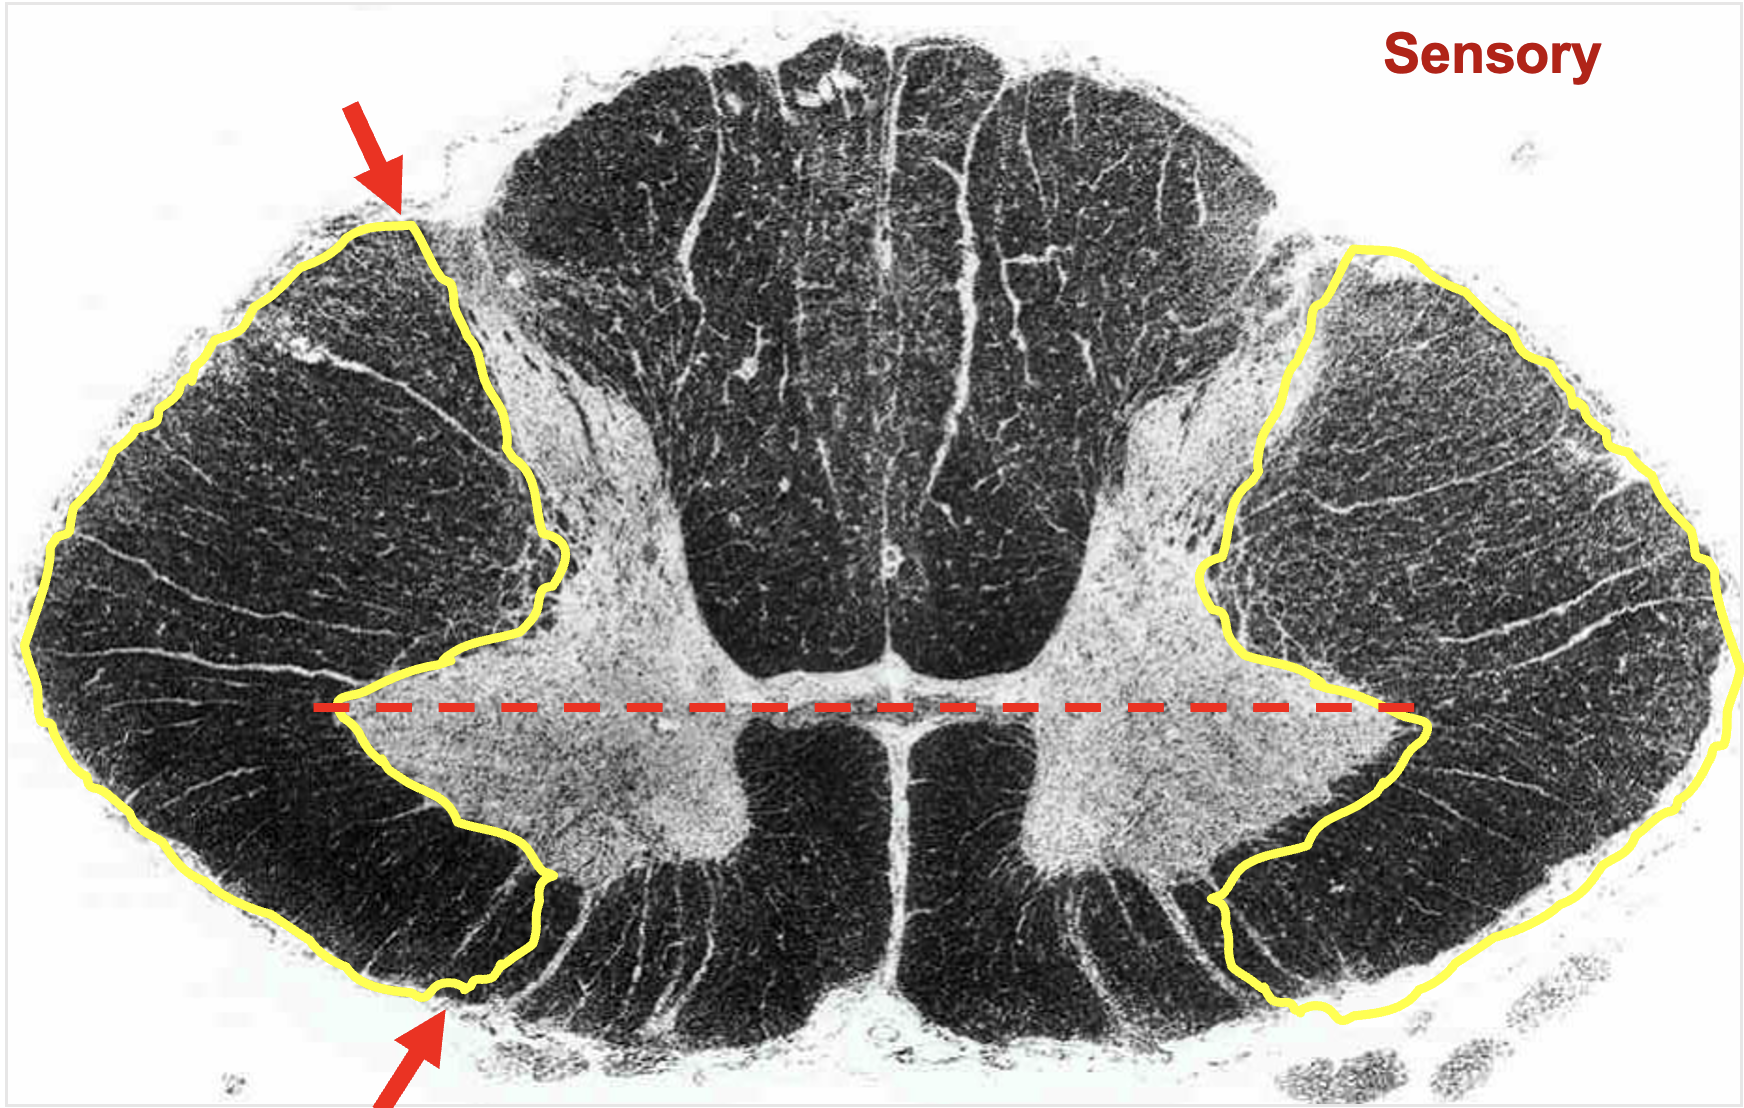

dorsal horn

dorsal rootlets

dorsal root

transmit sensory information from the periphery to the CNS

lateral funiculus

between lateral edge of dorsal and ventral horns; contains multple tracts

sensory and motor tracts

ascending and descending tracts